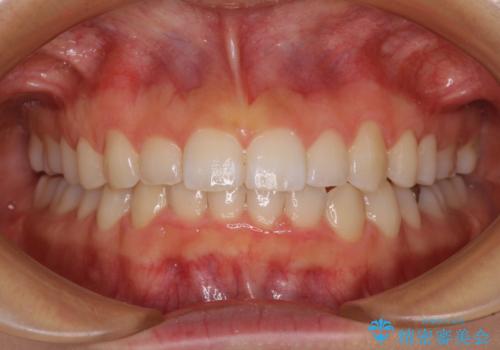

インビザラインによる狭窄歯列の拡大矯正

- 2年2ヶ月

上下顎ともに歯列全体の後方移動と側方拡大、IPR(歯と歯の間を削る)によってデコボコが解消するように設計し、インビザラインにより治療を行うこととしました。

治療途中で関西に転勤となってしまったため、東京に出張で来るタイミングに合わせて治療を進めることになりました。そのため、治療期間が長くなってしまいましたが、無事に仕上げることができました。